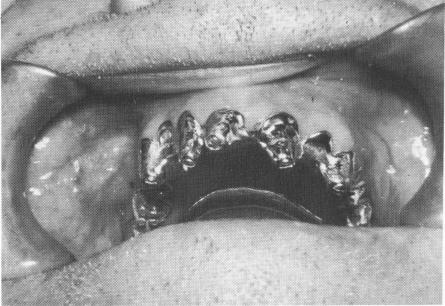

Fig. 10-250. The pins were secured to each other with acrylic cores that were prepared for full crown coverage.

The triplant pins were then drilled posteriorly through predetermined holes in the template and the excess length cut away (Fig. 10-249). The terminal ends of the pins were joined with quick cure acrylic, and the hardened acrylic cores were then prepared for full crown preparations (Fig. 10-250).